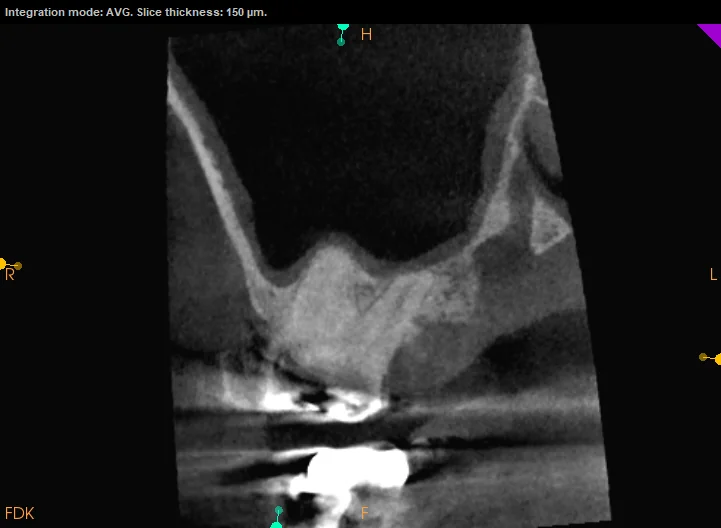

Our 30-minute consultation followed a systematic approach: detailed history taking (symptom timeline, aggravating factors, relationship to sinus congestion), clinical testing of all teeth in the affected quadrant (vitality, percussion, palpation), and CBCT imaging to evaluate teeth and sinus simultaneously in three dimensions—something standard radiographs cannot do.

The CBCT scan revealed subtle signs of a potential endodontic concern in one tooth that was invisible on standard radiographs. The sinus appeared mildly thickened but without frank infection. The critical distinction: two overlapping conditions—one dental, one sinus—each requiring a different management approach.

Why CBCT Was Decisive

CBCT imaging allowed us to:

• Evaluate both teeth and sinus in a single scan

• Detect early pathological changes invisible on periapical radiographs

• Map root proximity to the sinus floor precisely

• Establish a three-dimensional baseline for monitoring changes over time